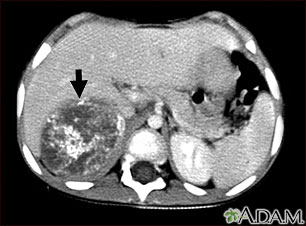

Neuroblastoma in the liver - CT scan

This CT scan of the upper abdomen shows a large tumor (neuroblastoma) on the person's right side (lower left side of picture). The tumor is behind the liver and is pushing the liver forward and may have possibly spread into the liver tissue.